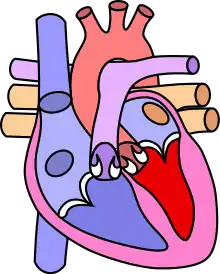

Tetralogy of Fallot (TOF), formerly known as Steno-Fallot tetralogy,[9] is a congenital heart defect characterized by four specific cardiac defects.[4] Classically, the four defects are:[4]

- pulmonary stenosis, which is narrowing of the exit from the right ventricle;

- a ventricular septal defect, which is a hole allowing blood to flow between the two ventricles;

- right ventricular hypertrophy, which is thickening of the right ventricular muscle; and

- an overriding aorta, which is where the aorta expands to allow blood from both ventricles to enter.

![]() | |

| Diagram of a healthy heart and one with tetralogy of Fallot | |

Four malformations

"Tetralogy" denotes four parts, here implying the syndrome's four anatomic defects.[2] This is not to be confused with the similarly named teratology, a field of medicine concerned with abnormal development and congenital malformations (including tetralogy of Fallot). Below are the four heart malformations that present together in tetralogy of Fallot:

| Pulmonary Infundibular Stenosis | A narrowing of the right ventricular outflow tract. It can occur at the pulmonary valve (valvular stenosis) or just below the pulmonary valve (infundibular stenosis).[4] Infundibular pulmonic stenosis is mostly caused by the overgrowth of the heart muscle wall (hypertrophy of the septoparietal trabeculae),[43] however, the events leading to the formation of the overriding aorta are also believed to be a cause. The pulmonic stenosis is the major cause of the malformations, with the other associated malformations acting as compensatory mechanisms to the pulmonic stenosis.[44] The degree of stenosis varies between individuals with TOF and is the primary determinant of symptoms and severity. This malformation is infrequently described as sub-pulmonary stenosis or subpulmonary obstruction.[45] |

| Overriding aorta | An aortic valve with biventricular connection, that is, it is situated above the ventricular septal defect and connected to both the right and the left ventricle. The degree to which the aorta is attached to the right ventricle is referred to as its degree of "override." The aortic root can be displaced toward the front (anteriorly) or directly above the septal defect, but it is always abnormally located to the right of the root of the pulmonary artery. The degree of override is extremely variable, with 5-95% of the valve being connected to the right ventricle.[43] |

| Ventricular septal defect (VSD) | A hole between the two bottom chambers (ventricles) of the heart. The defect is centered around the most superior aspect of the ventricular septum (the outlet septum), and in the majority of cases is single and large. In some cases, thickening of the septum (septal hypertrophy) can narrow the margins of the defect.[43] |

| Right ventricular hypertrophy | The right ventricle is more muscular than normal, causing a characteristic boot-shaped (coeur-en-sabot) appearance as seen by chest X-ray. Due to the misarrangement of the external ventricular septum, the right ventricular wall increases in size to deal with the increased obstruction to the right outflow tract. This feature is now generally agreed to be a secondary anomaly, as the level of hypertrophy tends to increase with age.[46] |